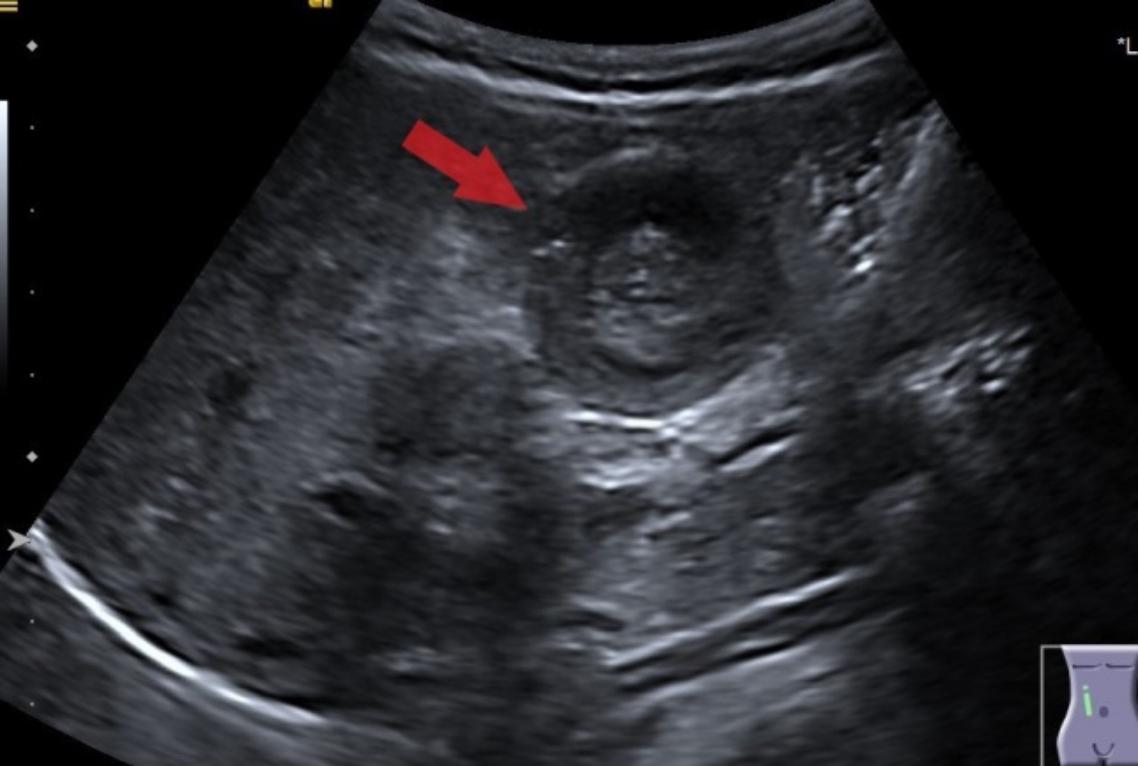

在小兒科急診醫師詳細詢問以及理學檢查後,發現男嬰跟他哥哥在上禮拜都有腺病毒感染的過去病史。細心的醫師為了排除腹部急症的可能性,立即施行腹部超音波,果不其然,在小朋友右上腹出現了腸子套住的超音波影像(圖1),準確診斷為嬰幼兒常見的腹部急症「腸套疊」。

張育瑞還特別提醒家長,對於已經患有胃腸炎的兒童來說,診斷腸套疊也會特別困難,因為急性腸胃炎也有可間歇性腹痛或者嘔吐。當無法區分急性腸胃炎跟腸套疊時,進一步的影像檢查就相當必要,而超音波檢查是檢測腸套疊的首選方法。在超音波中看到「同心圓」或「甜甜圈」的影像,代表腸內的腸層已經套住並黏膜重疊,才會產生如此影像(圖1)。